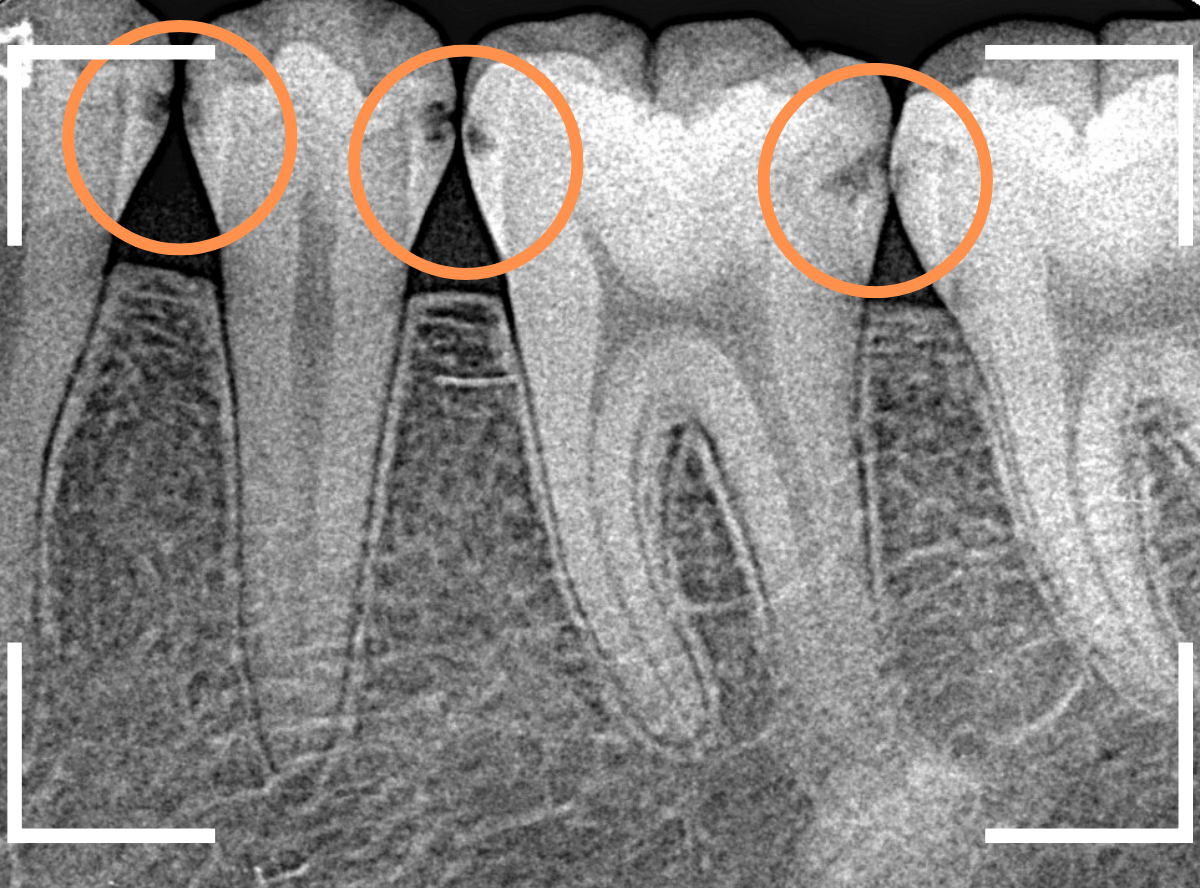

Case.22 痛みはないけど、歯のすきまから大きな虫歯

上の小臼歯の間が虫歯になっていた患者さんです。

症状はありませんし、見た目からも虫歯があるかはわかりませんでした。

レントゲン写真で確認します。

赤い線が虫歯、青い線が歯の神経です。

歯のすきまから両側に虫歯が大きく広がっているのが確認できます。

治療を開始します。

少し削ると、中からすぐに虫歯が出てきました。

ある程度、虫歯を除去したところで、う蝕検知液で確認します。

赤く染まっている部分が虫歯です。

まだまだ虫歯が中で残っている状況で、かなり深い虫歯なのが確認できます。

全ての虫歯を除去しました。

レントゲン写真からある程度確認出来ましたが、歯の神経スレスレまで虫歯が進行していました。

ここまで虫歯が進行していても、全く症状を感じない事も多いです。

そして、ある時急に痛みを感じるのです。

虫歯は急に進行しません。

治療後の定期検診で確実に食い止めましょう。